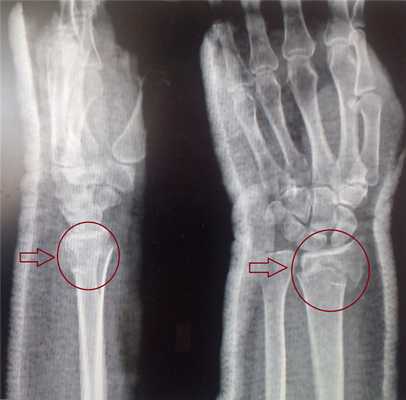

До операции: